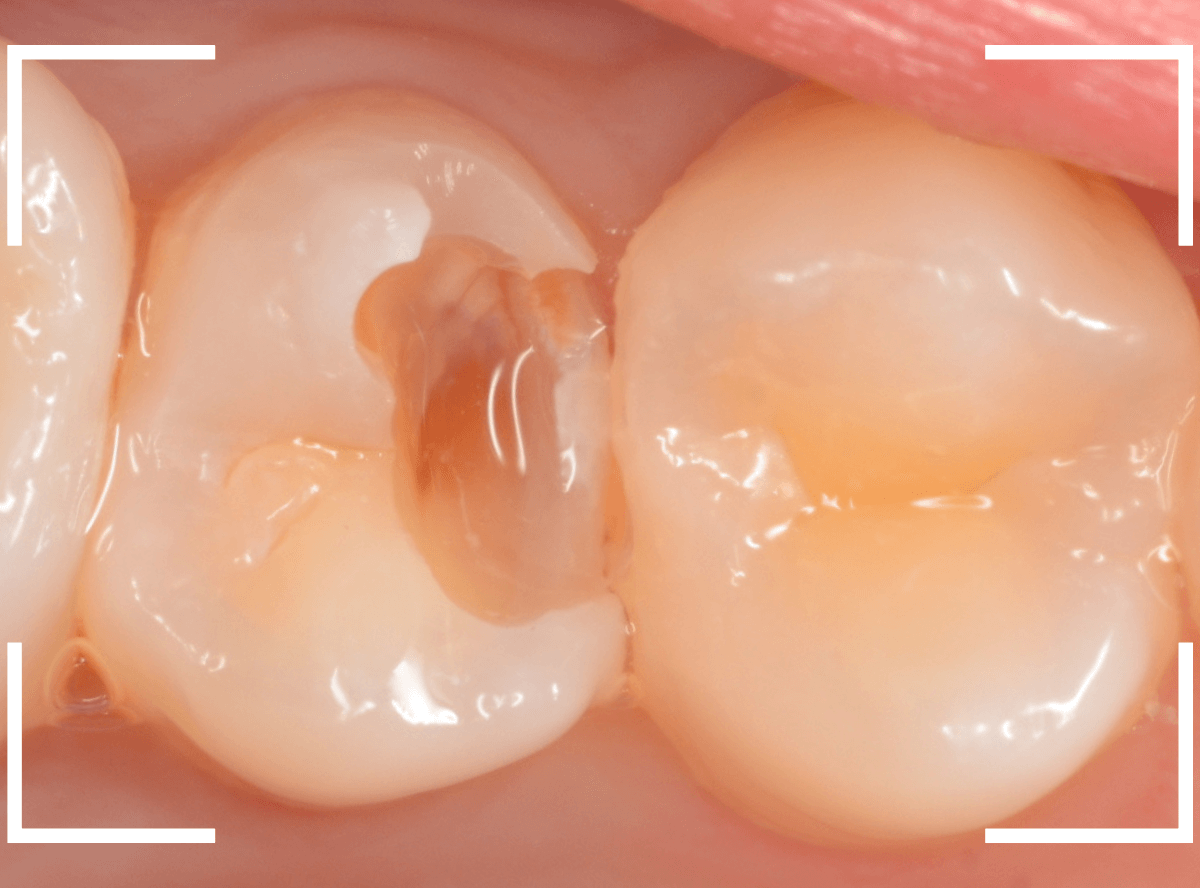

Case.30 上の奥歯のセラミック治療

メンテナンス中に、虫歯が見つかった方のケースです。

大きな虫歯でしたので、しばらく経過観察しましたが、特に症状もありませんでしたので、患者さんの希望に伴い、ジルコニア・インレーで治療をします。

セラミックが精密にsetできるように、歯をトリミングします。